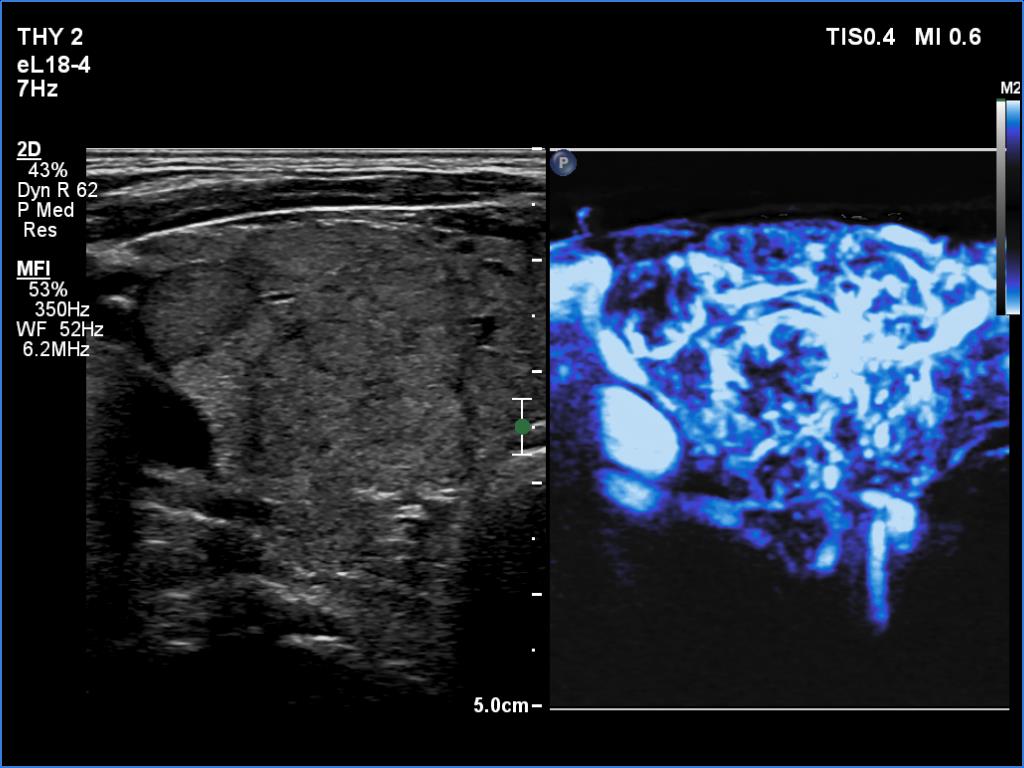

Lymphocytic thyroiditis - case 609

Follow-up investigation 6 years after the first visit (ultrasonographic picture 5)

Right lobe, transverse scan, microflow imaging. Note the presence of vessels according to the connective tissue bands which divide the lobe into smaller pseudolobules.